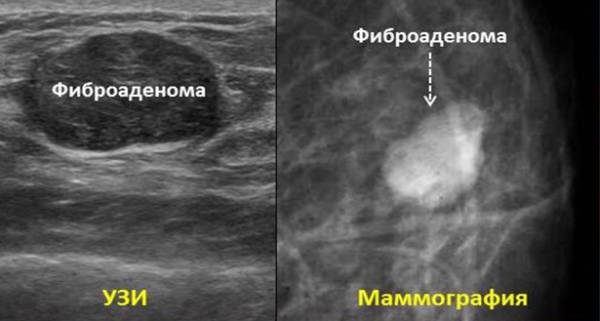

- УЗИ. Это основной диагностический способ, позволяющий определить всек основные параметры.

- Маммография (специальная рентгенография). Она проводится для определения срока существования образования, в частности по пропитке фибромы кальциевыми солями.